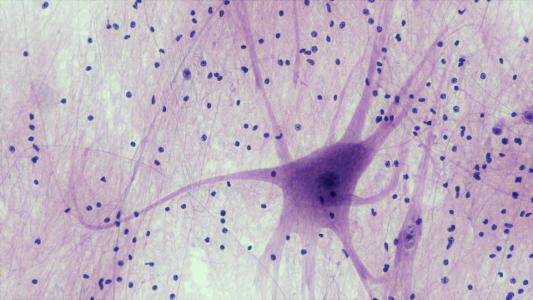

The eternal sunshine of the stressed out mind

Researchers at Cambridge University have finally figured out how the brain stops stressful thoughts and memories...

A prosthetic memory can help you remember

Scientists have figured out how to hack the brain's memory.